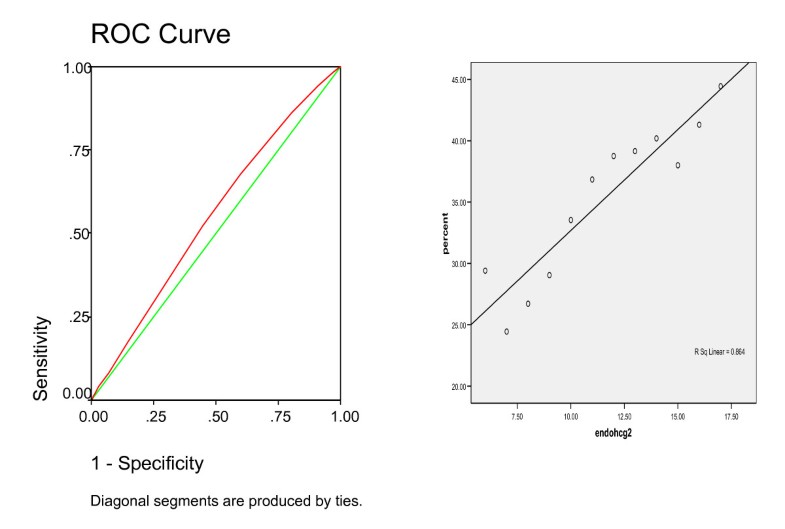

The Correlation Between Endometrial Thickness And Outcome Of

Pdf The Correlation Between Endometrial Thickness And .

The Correlation Between Endometrial Thickness And Outcome Of .